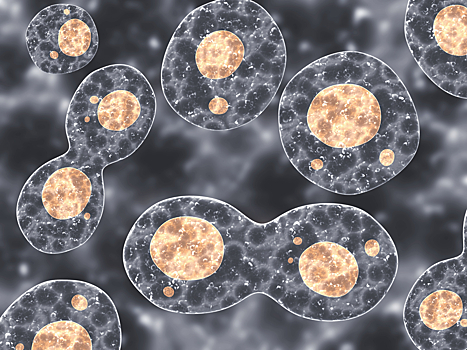

Паразитический организм неглерия Фоулера, вызывает первичный амебный менингоэнцефалит, который часто заканчивается летальным исходом.

"Лейк-Джексон проинформировали о наличии неглерии Фоулера, пожирающей мозг амебы, в сети водопровода", - сообщается в пресс-релизе, опубликованном на сайте города.

Департамент здравоохранения округа Бразориа сообщил властям города, что из-за неглерии Фоулера в больницу попал шестилетний мальчик. Три из 11 взятых специалистами проб показали, что паразит находится в системе водоснабжения.